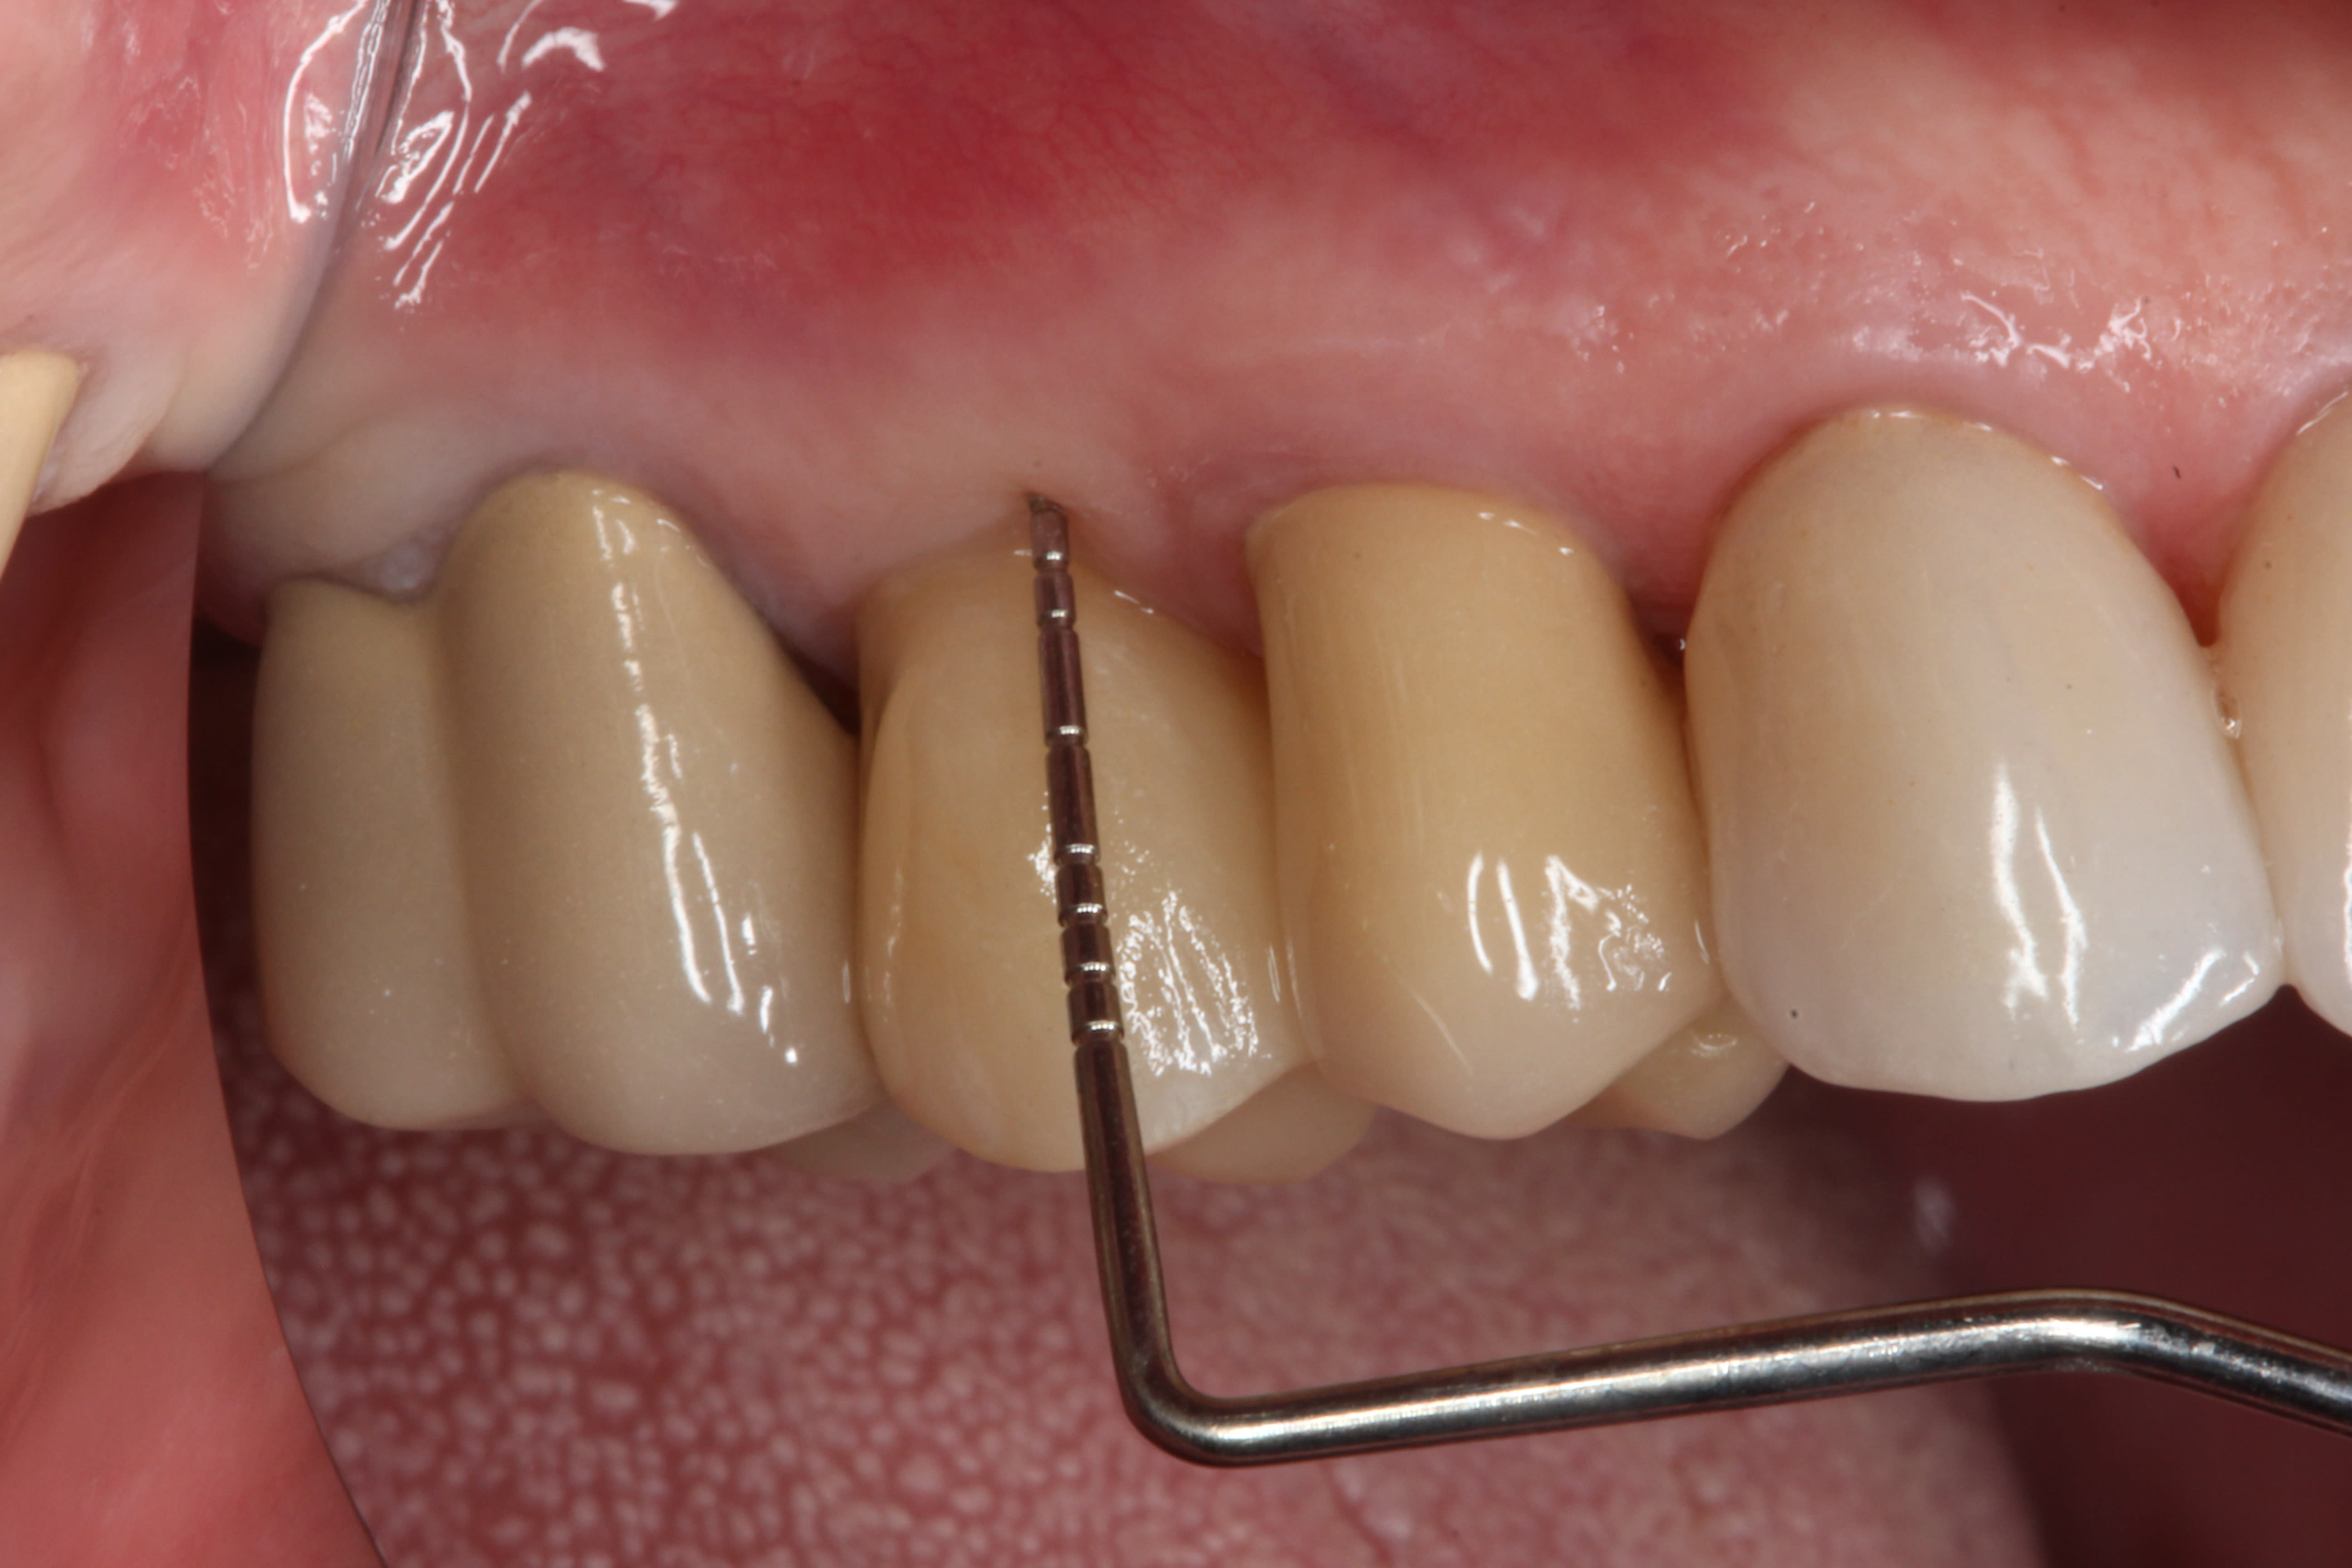

The final impression (closed tray) was obtained in April 2012. The final ceramic crowns (IPS e.max Ceram) and custom porcelain-veneered, regular-diameter (RD) UCLA abutments (Genesis; and Creation CC, Jensen Dental, www.jensendental.com) (Figure 24, shown with PFM crowns and retention screws) were delivered in May 2012. Using a platform-switched connection, the abutments were torqued to 30 Ncm, the access holes sealed with Teflon, and the final crowns cemented with RelyX Unicem. Figure 25 through Figure 28 show the final IPS e.max Ceram crowns from periapical, facial, and incisal views, with a midfacial PD of 3 mm at the 18-month follow-up (Visit 7). A thick biotype is evident in Figure 26, as determined by the inability to detect the outline of the periodontal probe inserted below the restoration’s gingival margin.50 This image also demonstrates an excellent esthetic outcome.